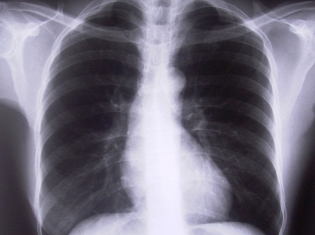

(RxWiki News) The best way to avoid lung cancer is to never pick up the smoking habit. Unfortunately, that's no guarantee for skirting deadly lung cancer disease.

Never smokers who develop lung cancer have different types of tumors than those that form in smokers.